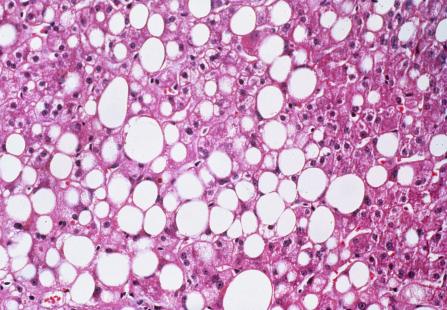

Exceptionnelle chez le sujet maigre, la NASH survient le plus souvent dans un contexte d’insulinorésistance, chez des patients ayant un syndrome métabolique, mais sans consommation excessive d’alcool (< 20 g/jour), même si une consommation d’alcool a priori non excessive, peut l’être chez un diabétique par exemple. Liée à la sédentarité et à l’obésité, la NASH progresse en France, comme le syndrome métabolique. Elle touche aujourd’hui 1 % de la population française. Adultes mais aussi enfants et adolescents peuvent en être atteints. Seule l’anamnèse permet d’éliminer une stéato-hépatite d’origine alcoolique, d’histologie assez comparable.

« Devant un ou plusieurs éléments du syndrome métabolique (diabète de type 2, HTA, obésité, dyslipidémie) la première difficulté est de penser à faire un bilan hépatique. La deuxième est de ne pas se rassurer s’il est anormal (augmentation des transaminases et/ou des gamma GT) », explique le Pr Philippe Sogni, hépatologue à l’hôpital Cochin. Déterminer si ces anomalies sont liées ou non à une NASH n’est pas évident. « Le mieux est d’envisager un avis spécialisé », précise le spécialiste. Les méthodes non invasives classiques d’évaluation de la fibrose (fibroscan, fibrotest) permettent un premier screening. « Un fibroscan inférieur à 8 Kpa élimine une fibrose avec un risque d’erreur < 3 %, donc évite de nombreuses biopsies inutiles », précise le Dr Patrick Delasalle, hépato-gastroentérologue à Grasse, président du club de réflexion des cabinets et groupes d’hépato-gastroentérologie (CREGG). Le FIB-4, un marqueur simple non invasif (âge, transaminases, plaquettes) fait sans doute aussi bien. En pratique, une biopsie hépatique est souvent nécessaire pour différencier la stéatose simple de la stéato-hépatite et préciser le degré de fibrose.